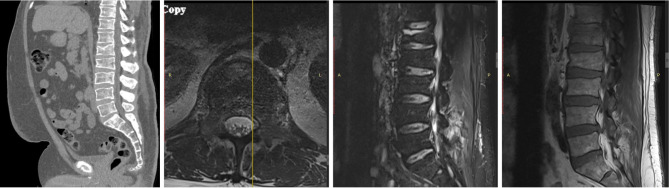

Case description: We present a clinical case of a 59-year-old diabetic male patient with a recent foot ulcer, positive for Corynebacterium striatum and Enterococcus. Shortly after discharge, the patient was admitted for signs of septicemia positive for Corynebacterium striatum and Pseudomonas aeruginosa. The patient had also sustained an acute L1 compression fracture at the time of septic presentation. A KP was performed, just 10 days after original septicemia diagnosis. 5 months later, the patient presented with continued incapacitating back pain at the operative site, and a diagnose revealing osteomyelitis at the location of the L1 KP positive for Corynebacterium striatum, treated with vancomycin and daptomycin. The cement and surrounding bone were compromised and instability developed, requiring an L1 vertebrectomy with T9-L4 posterior fusion with allograft. The patient has been followed for 1.5 years postoperatively with full recovery, decreased pain, and improved quality of life. We discuss the importance of KP safety in the setting of recurrent systemic infection.

Abstract Image